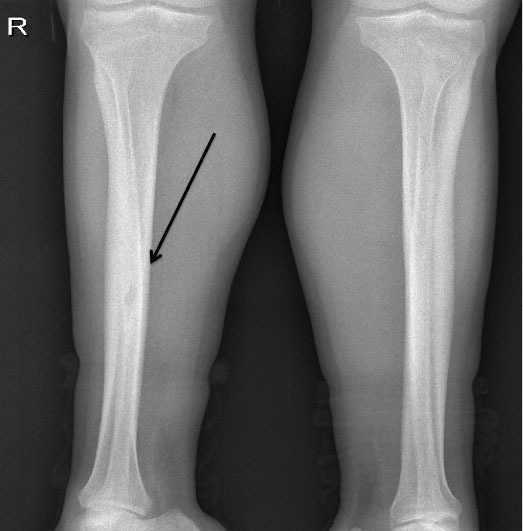

Presentamos el caso de un varón de 38 años con insuficiencia renal crónica terminal secundaria a nefropatía por reflujo, en programa de hemodiálisis desde los 23 años. Presentaba hiperparatiroidismo secundario tratado con paricalcitol por intolerancia digestiva a cinacalcet, con hormona paratiroidea (PTH) en torno a 1900 pg/ml. Consultó por una tumoración indolora, dura y sin signos inflamatorios, de un mes de evolución en el hombro izquierdo (figura 1). La serie ósea (figura 2 y figura 3) y la tomografía axial computarizada cérvico-torácica (figura 4) mostraron una imagen ovoidea, hipodensa y de borde no escleroso en la diáfisis de la tibia derecha y lesiones osteolíticas expansivas, con importante adelgazamiento de la cortical en las zonas distales de ambas clavículas, la mayor (4 cm de diámetro) en el lado izquierdo, que corresponden a tumores pardos debidos al hiperparatiroidismo secundario. Se realizó una paratiroidectomía total, observándose adenomas en las glándulas izquierdas y descenso inmediato de la PTH hasta 0,3 pg/ml.

Figura 4. Imagen de tomografía axial computarizada que corresponde a un tumor pardo en la clavícula izquierda